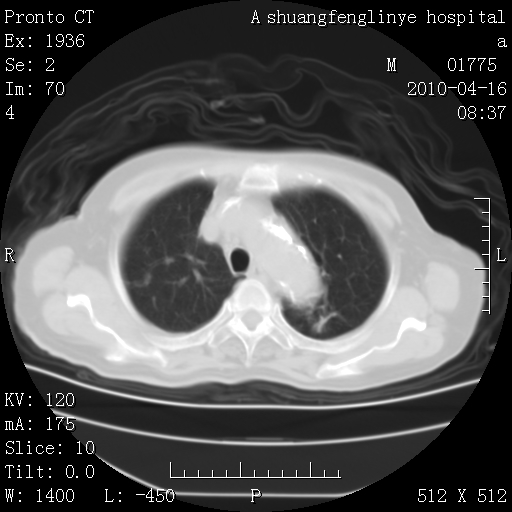

标题: CT25784:咳痰、请会诊!结核? [打印本页]

标题: CT25784:咳痰、请会诊!结核?

考虑左肺上叶增殖灶、纤维灶。

支持结核

老年肺间质纤维化,肺动脉高压-----肺心病。

慢支肺气肿,左上陈旧性结核,主动脉冠脉钙化

1)左肺上叶结核(纤维、增殖病灶)。2)冠状动脉及主动脉钙化。

1)左肺上叶结核(纤维、增殖病灶)。2)冠状动脉及主动脉钙化。肺动脉高压